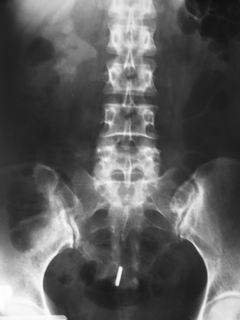

• Một điều chắc chắn rằng, khi amonium càng bám nhiều sỏi sẽ lớn dần. Nó tiếp tục lớn lên và quấn quanh nhân sỏi cho đến khi toàn bộ khoảng trống trong bể thận đều được lấp đầy bởi sỏi. Lúc đó nó được gọi là sỏi sừng nai - sỏi san hô (staghorn calculus) khi ấy trên x quang có hình ảnh như gạc của con nai.